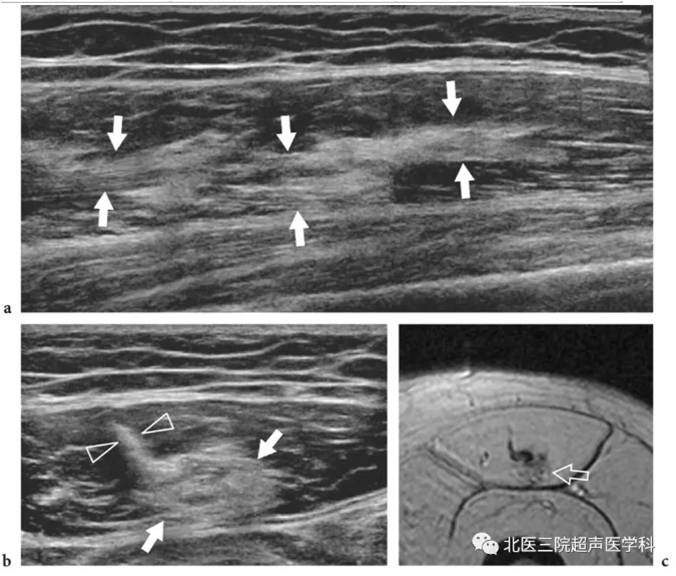

股直肌损伤愈合期(晚期)。患者有股直肌肌腱拉伤史,a长轴宽景成像、b短轴切面,均显示肌肉内中心腱旁的模糊斑点状高回声区,代表残留的瘢痕组织,通常在严重创伤或从事体育活动过早的病例中,c为相应的T2加权轴向的梯度回波成像